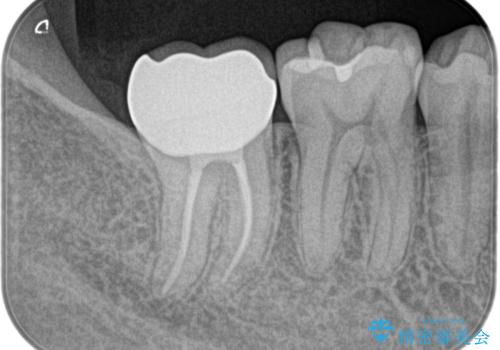

奥歯が痛い。精密根管治療〜オールセラミッククラウン

奥歯の根管治療~オールセラミッククラウン